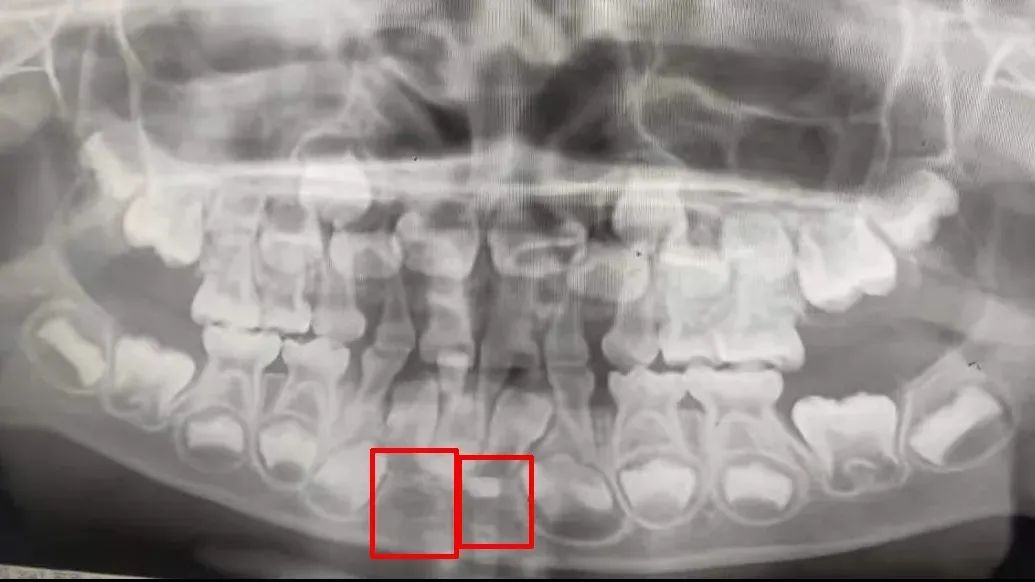

▲标记处为:儿童换牙期缺失牙,乳牙脱落后则会缺牙。